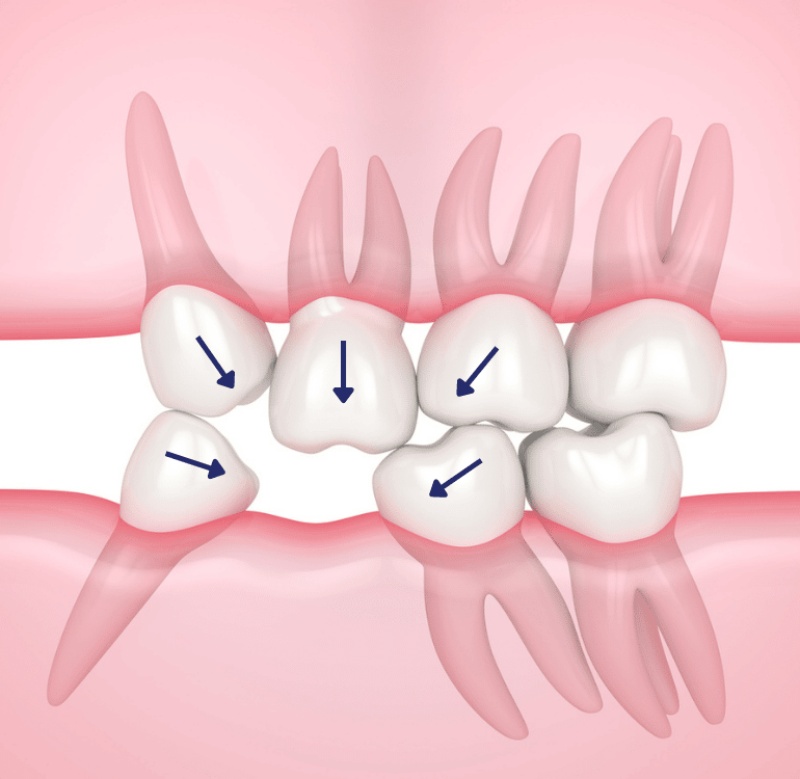

What Happens If We Don’t Replace a Lost Tooth?

If a tooth is extracted and not replaced, it can lead to significant problems over time. Normally, our teeth are constantly shifting, though we may not always notice it. Here are some issues that may arise if a lost tooth is not replaced:

- Adjacent teeth may shift, tilt, or fall out: If left untreated, this can cause more teeth to be lost, possibly leading to multiple teeth being affected.

- Improper bite alignment: This can lead to problems with the jaw joint, causing discomfort and issues with chewing.

- Changes to facial structure: The absence of a tooth can affect the overall shape of the face, leading to a sunken or uneven appearance.

- Increased pressure on remaining teeth: Without a replacement tooth, more pressure is placed on the remaining teeth, which could result in them becoming more prone to cracking, chipping, or breaking due to excessive force.

Therefore, it is highly recommended to replace a lost tooth, whether with a dental implant, bridge, or even dentures, to avoid further complications down the road.